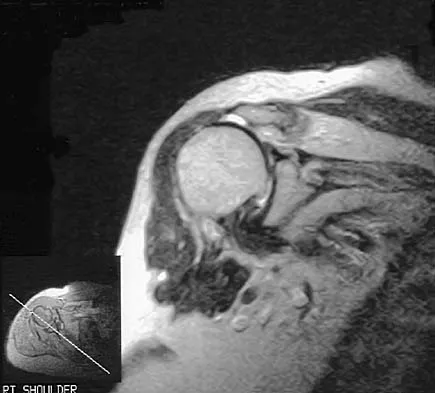

An 11-year-old boy has right shoulder pain and has been unwilling to use the arm after throwing a baseball in a Little League game 3 weeks ago. Examination reveals upper arm and shoulder tenderness with swelling. A radiograph and MRI scan are shown in Figures 27a and 27b. Management should consist of

Explanation